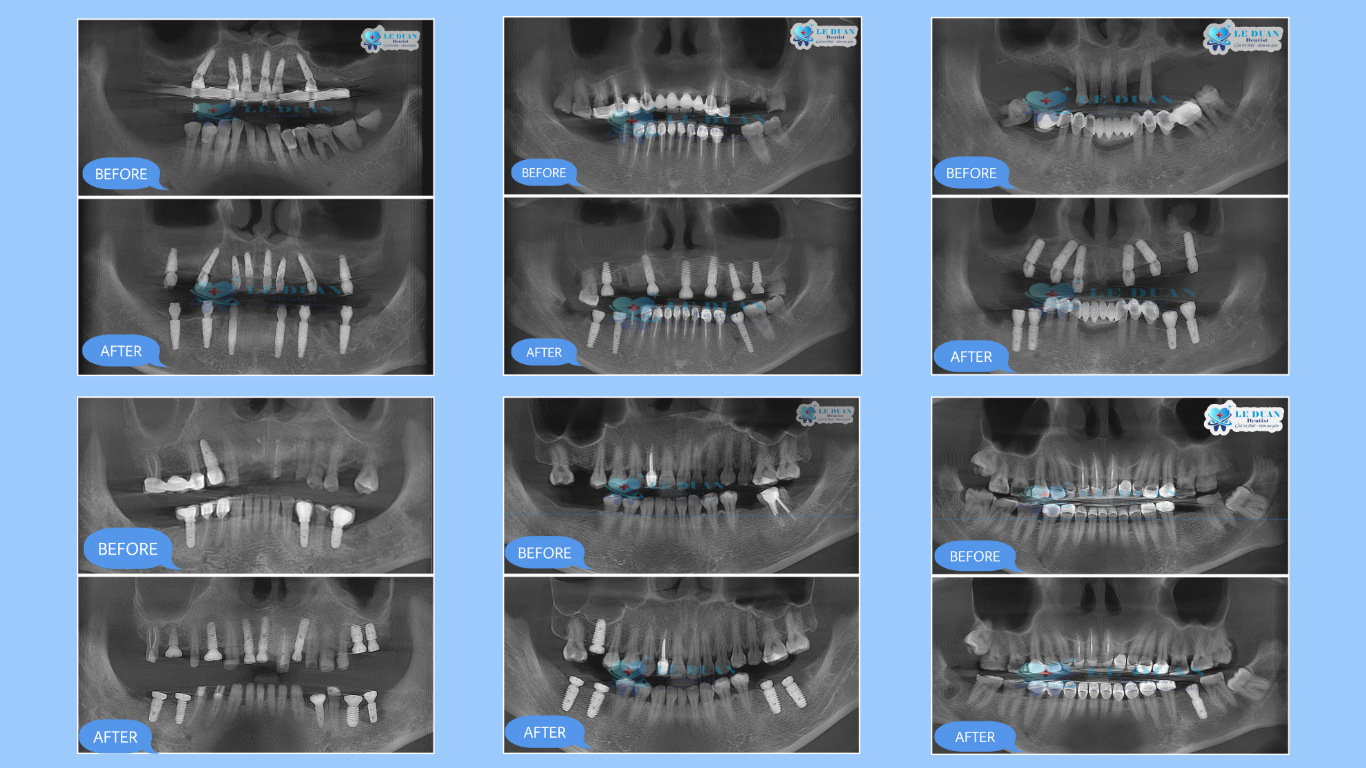

3. Các ca lâm sàng thực tế được thực hiện tại Nha khoa Lê Duẩn

Các ca lâm sàng trực tiếp tại Nha khoa Lê Duẩn — từ ca đơn lẻ đến phục hình toàn hàm. Chúng tôi sử dụng thiết bị y tế hiện đại và Implant chính hãng, có nguồn gốc xuất xứ rõ ràng.